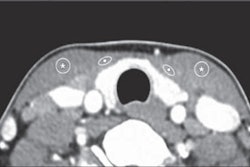

Seventeen patients had a total cumulative effective dose of more than 100 mSv, a value associated with a substantial increase in risk for cancer-related mortality. Of the total radiation dose, 76% was due to CT scanning.

The median number of radiologic procedures was 4.3 (range, 2.3-6.3) per patient-year. CT exams accounted for an outsized 76% of the total cumulative effective dose, but they comprised only 19% of the total number of radiological procedures.